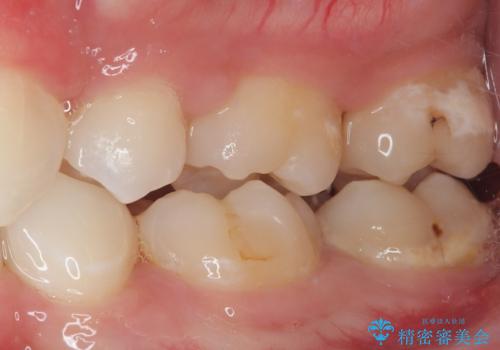

- 今回ご紹介するのは、

「全体的なデコボコ(叢生)」「上下の正中のずれ」 を主訴として来院された20代男性の患者様の症例です。

叢生が強く、歯が並ぶスペースが不足していたため、

上下左右の第一小臼歯を抜歯して、矯正治療のための適切なスペースを確保する計画としました。

上顎左側第一大臼歯に齲蝕が認められたため、矯正治療終了後に 精度の高いセラミックインレー にて修復治療を行いました。